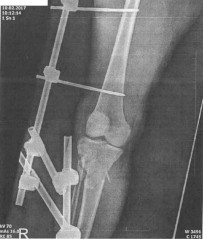

Moniku před pár lety na přechodu pro chodce srazilo auto. Utrpěla vážná zranění hlavy, ramene a nohy. Transportovali ji vrtulníkem do krajské nemocnice, kde podstoupila několik náročných operací. Lékaři jí tam doslova zachránili život